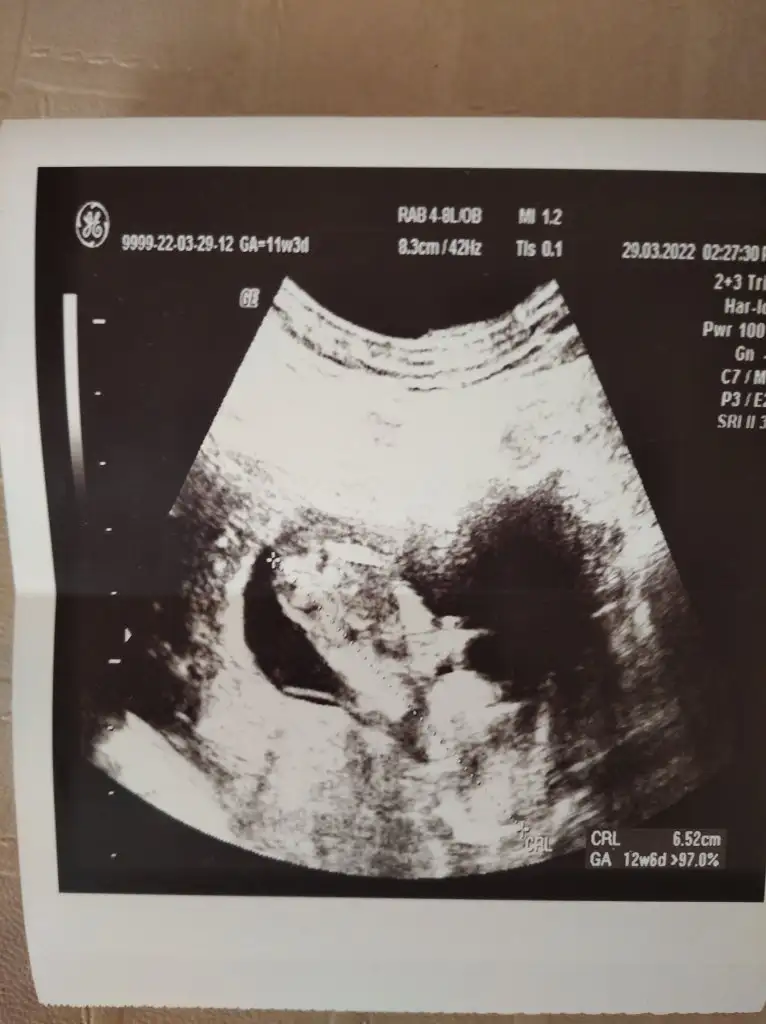

Arkadaşımın da ultrason fotosunu atmıştım ona da yorum yapar mısınız? 12 haftalık karından.